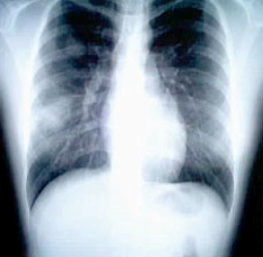

SARS患者患病五天的胸透照片